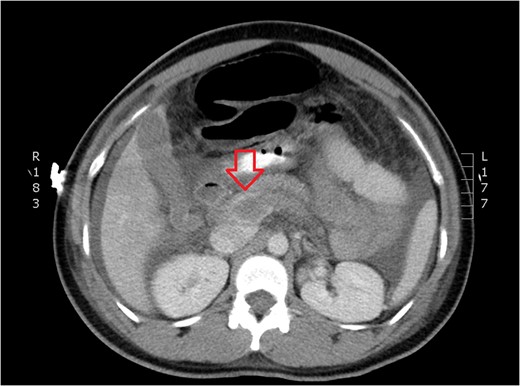

CT of dilated portal vein and extension of thrombosis (axial view).

The patient presented to the emergency room the evening of POD 3 with emesis and obstipation. Her vital signs and laboratory values were normal. An x-ray showed small bowel dilation and she was readmitted for postoperative ileus. A nasogastric tube was placed and the patient was started on IV fluids. Upon worsening pain and tachycardia on POD 4, a computed tomography (CT) scan with triple contrast was obtained. The CT scan showed evidence of PVT (Figs 1–3). The patient was transferred to the ICU and started on a therapeutic heparin. She improved clinically and was discharged home with rivaroxaban on POD 8. A hematologic evaluation was negative for disorders of factor V Leiden, antithrombin III, homocysteine and cardiolipin.